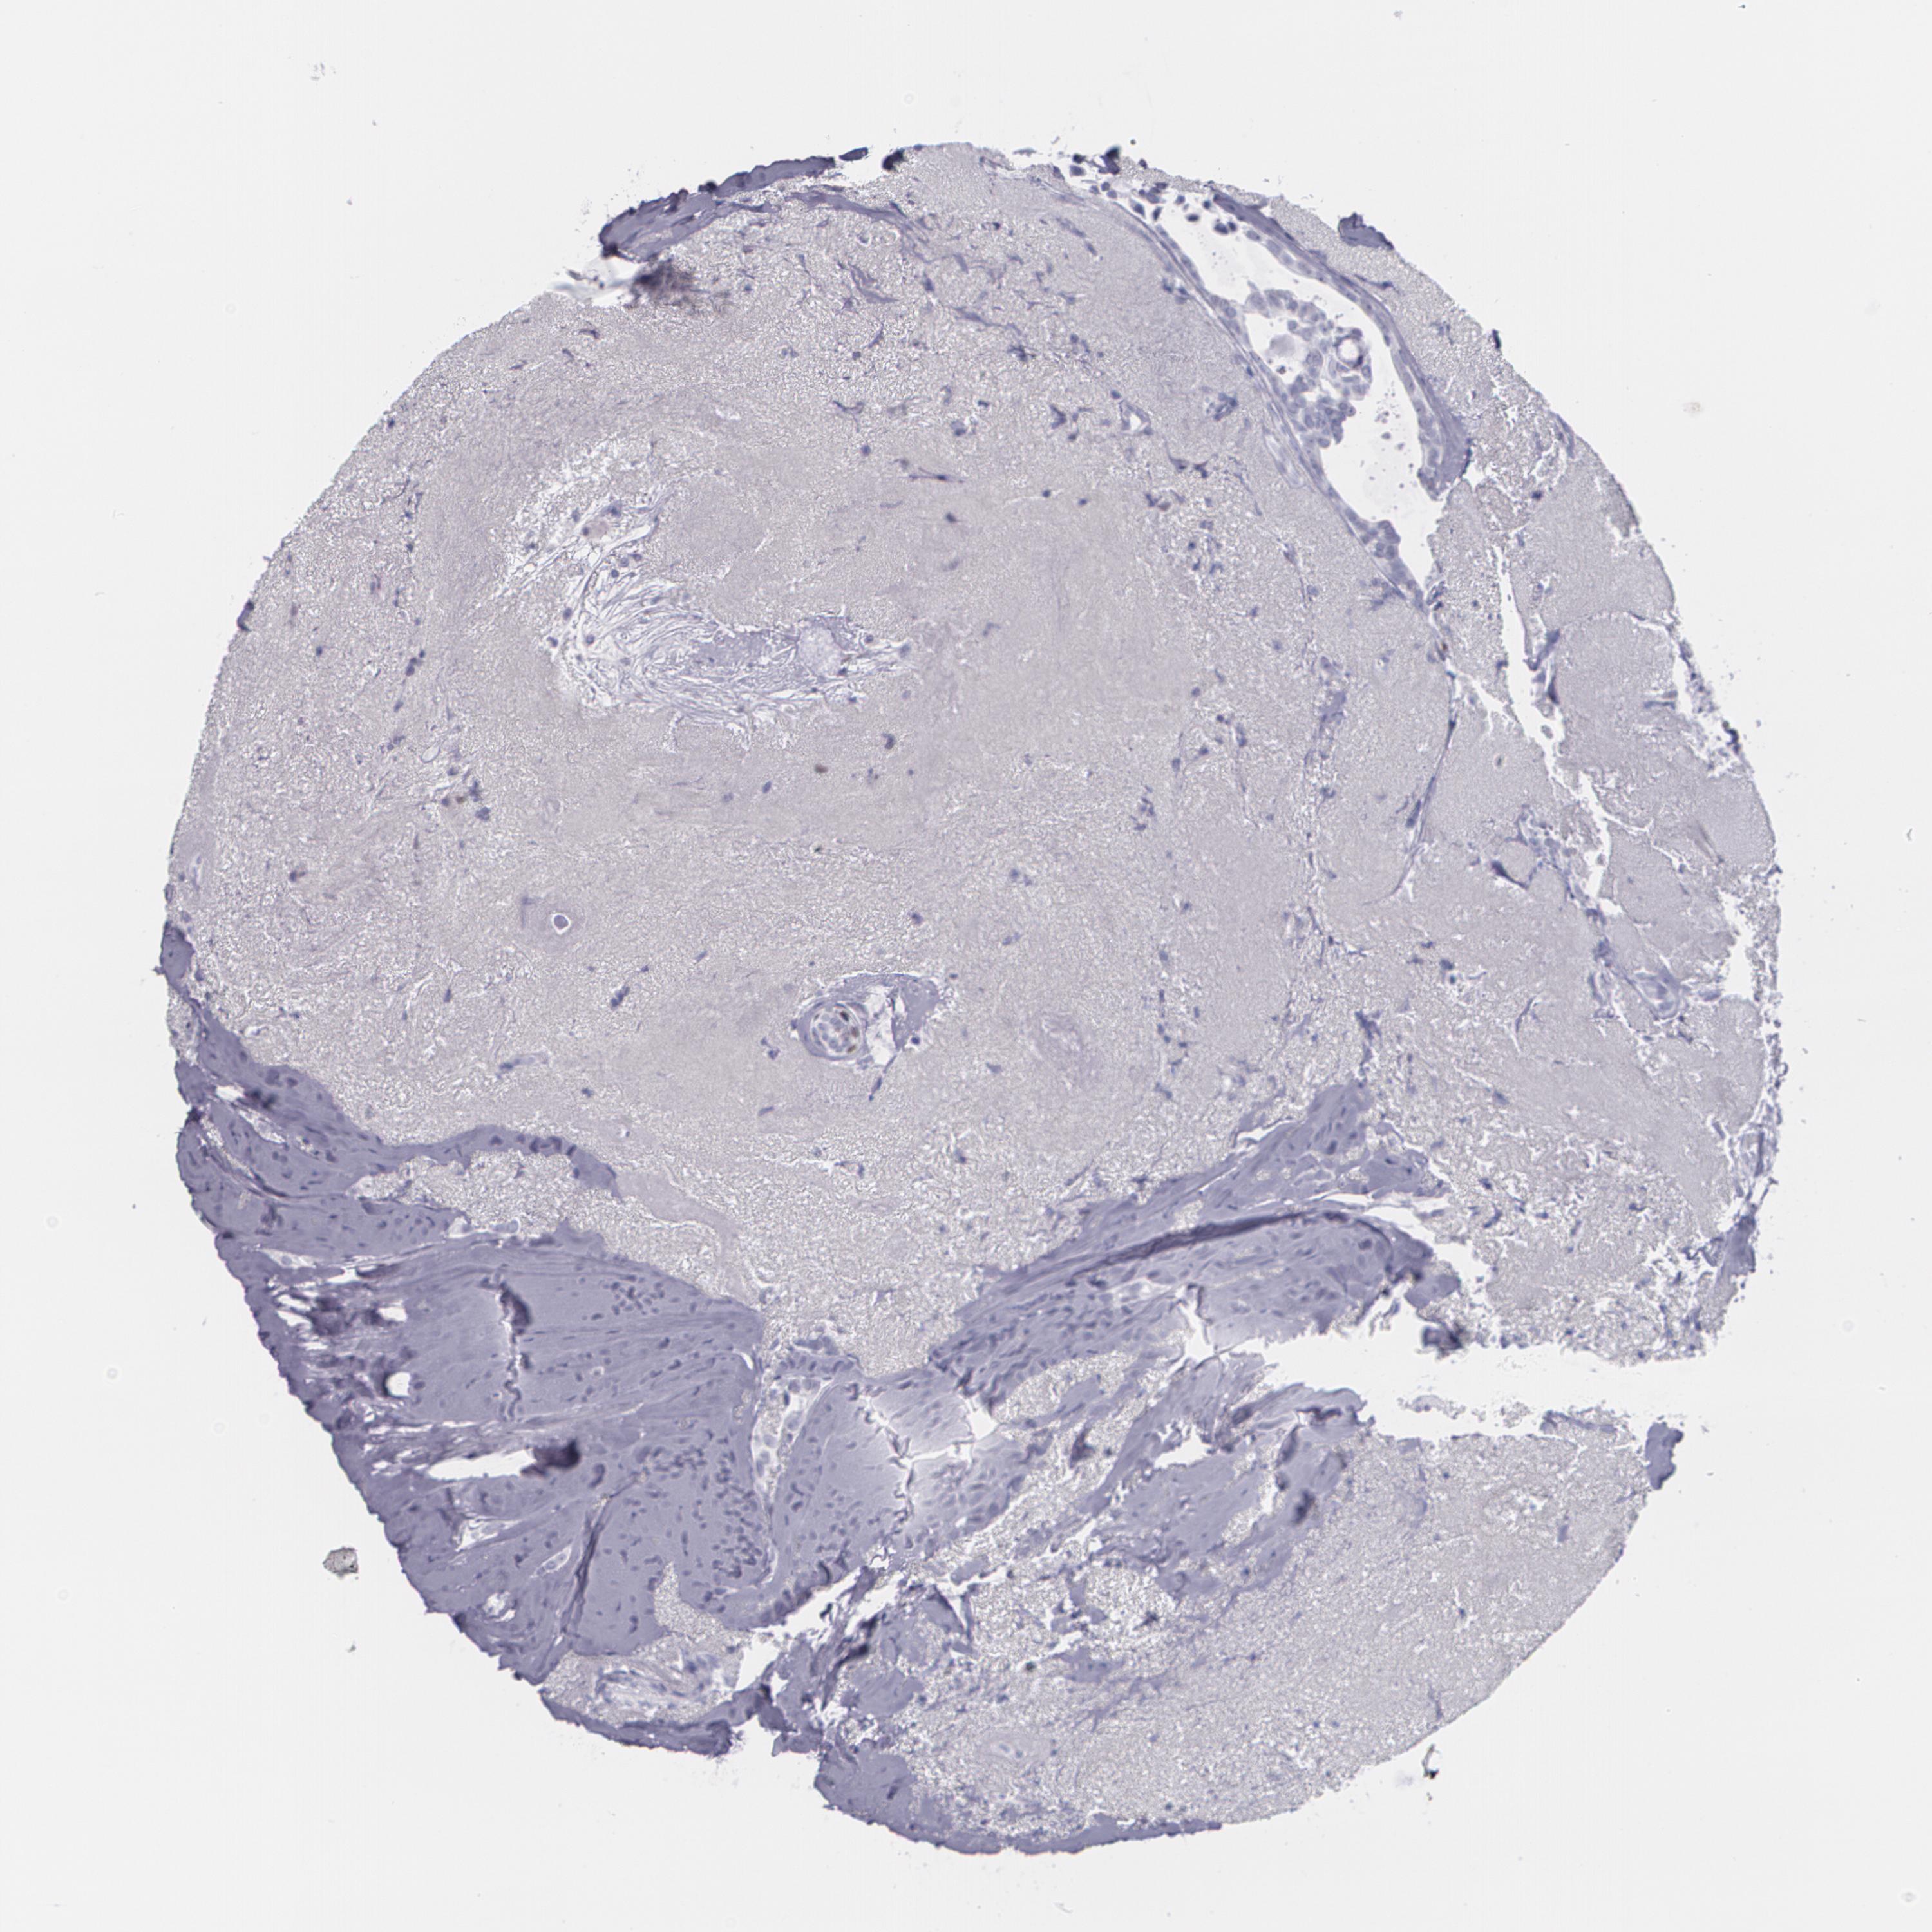

CANCER BREAST CANCER Show tissue menu

BRCA TCGA BRCA VALIDATION PROTEIN EXPRESSION